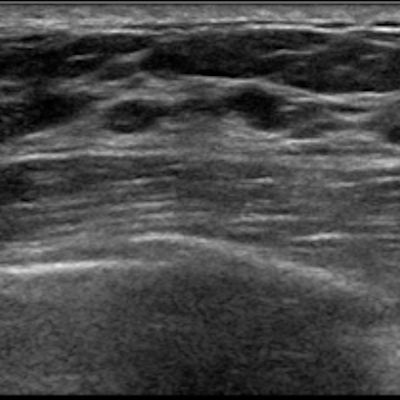

For example, researchers from Froedtert Hospital in Milwaukee, WI, found that morphologic features of axillary nodes on sonography are reliable indicators in predicting metastasis. Find out what these features are in this edition’s featured article.